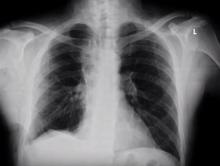

This video demonstrates sharp dissection of vascular structures during VATS lobectomy.